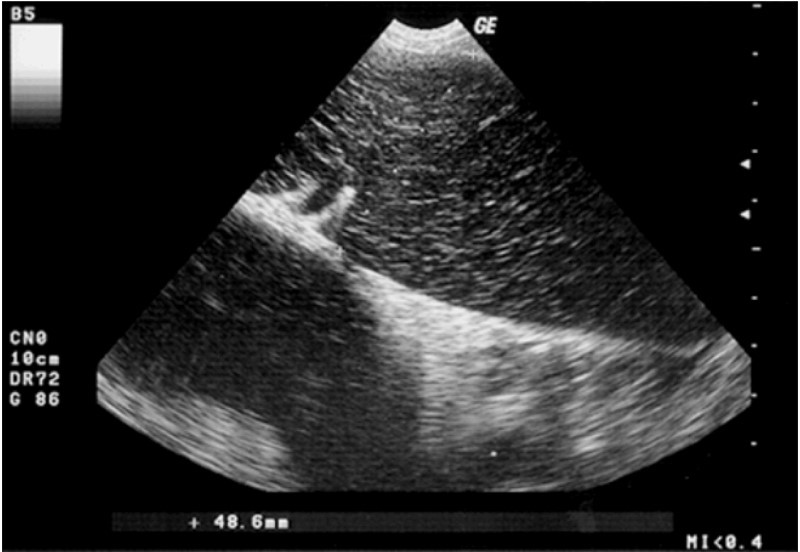

سونوگرافی کبد در درجه اول در موارد بیماری های مزمن (نارسایی کبدی، نفوذ پارانشیم چربی، ضایعات پارانشیمی کانونی) و در پیگیری آنها اندیکاسیون دارد. ویژگیهای تودههای منبسط اولیه/متاستاتیک کبد باید در نظر گرفته شود. وجود کیست های پر از مایع کبدی در گربه ها ممکن است با یک بیماری مادرزادی به نام بیماری کلیوی سیاستی (PKD) مرتبط باشد که اغلب در گربه های اگزوتیک و ایرانی مشاهده می شود. توصیف بدخیمی ندول های پارانشیمی متعدد کبدی را می توان با استفاده از ماده حاجب اولتراسونوگرافی مطالعه کرد. ارزیابی فاز ورید پورتال قادر است بین ندول های خوش خیم و بدخیم با حساسیت و ویژگی بالا تمایز قائل شود همانطور که در پزشکی انسان شرح داده شده است. ارزیابی سونوگرافی از کیسه صفرا و مجرای صفراوی مشترک ممکن است ضخیم شدن دیواره را نشان دهنده کولسیستیت باشد. محتویات آن با "ظاهر الگوی کیوی" رایج ممکن است وجود موکوسل را نشان دهد (شکل 1). سنگ کیسه صفرا، توده های منبسط شده، انسداد مجرای صفراوی مشترک از دیگر شرایطی هستند که می توان آنها را با سونوگرافی توصیف کرد. ارزیابی داپلر جریان ورید پورتال، در صورت نشان دادن، ممکن است شرایط فشار خون پورتال یا شرایط شانت کاوا پورتال را مشخص کند.

شکل1. موکوسل در سگ ماده 12 ساله نژاد مخلوط: اسکن اریب ساژیتال کیسه صفرا. در مجرای بیهوشی کیسه صفرا، ساختارهای پژواک حاکی از "الگوی کیوی" قابل مشاهده است.